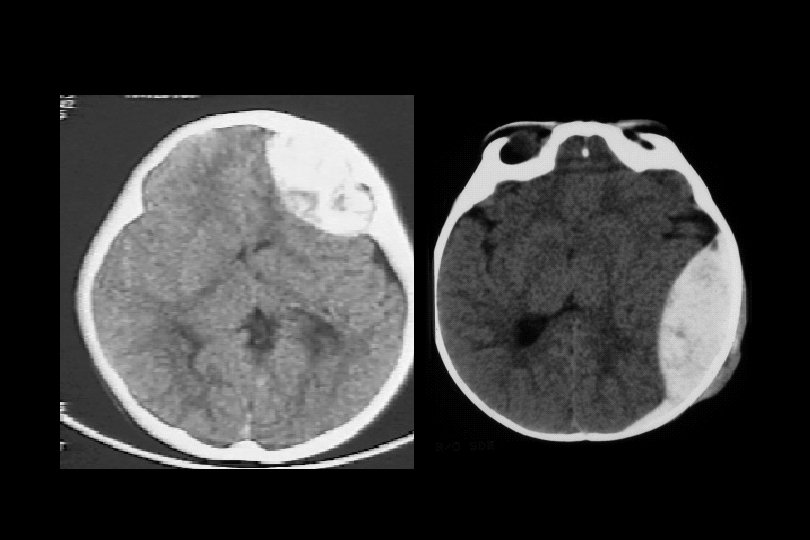

Epidural Hematom • A. meningica media • “lucid interval” • erken cerrahi mortalite: % 0

Subdural hematom • daha çok venöz kaynaklı • basit veya komplike olabilir! • Her şeye karşın mortalite % 40 -60